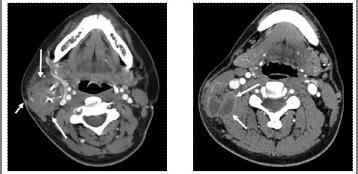

3.2颈面部肿大淋巴结的CT征象:转移性淋巴结肿大一般为中等密度,较均匀一致,有的有中央低密度区,提示有坏死囊变灶,边缘清楚或不清楚,由于有多个淋巴结融合,常有分叶改变,增强后以周边强为主,个别为均匀强化,或中央有低密度无强化区,恶性淋巴瘤淋巴结肿大密度均匀或中等密度,肿大淋巴结边缘清,增强后一致强化[3]。淋巴结结核的淋巴结肿大一般都为类圆形,周边密度均匀,中央有低密度区,提示有干酪样坏死区,边缘和转移性淋巴结肿大相比一般均有清晰边缘可见,增强后均匀强化,干酪坏死区不强化或表现不规则强化。淋巴结炎引起的淋巴结肿大密度略低于周围的肌肉组织,界限清楚,增强后均匀强化(见表2)。

3.3 CT分辨率高,特别对颈部相对紧密的部位能够很好显示其解剖结构,对颈部淋巴结肿大有其特殊诊断价值。CT不仅能够清晰显示肿物大小与周围组织结构。同时还可以对其性质作出准确判断。由于恶性肿瘤生长代谢旺盛,CT常能显示突破包膜向外侵润生长的改变和出现中央密度减低区及边缘环形强化,有时可显示肿块与血管壁的关系,在癌性病灶淋巴结转移中判断淋巴结外形轮廓与周围组织的关系时,淋巴结包膜屏障一旦被破坏其生存率明显降低,复发率明显提高[4]。颈部淋巴结多位于颈静动脉间隙内侧和后方,有时压迫血管向内侧和后方移位,舌骨上区颈动脉间隙淋巴结肿大可使颈动静脉分离,增强CT扫描有助于定位及定性诊断。另外,淋巴结的大小会在一定程度上影响CT诊断的准确率[5]。直径 3.4颈部淋巴结肿大对于炎症、肿瘤、结核的诊断意义重大,特别对于临床早期诊断、早期治疗都有重要意义,单纯炎症所致的淋巴结肿大,淋巴结常以单发的孤立的结节为主要表现,相互之间很少融合,有比较完整的包膜,与结核相比无钙化。而肿瘤所致的淋巴结转移有明显的肿瘤特点,例如无完整的包膜,相互之间经常融合与周围正常组织界线不清。